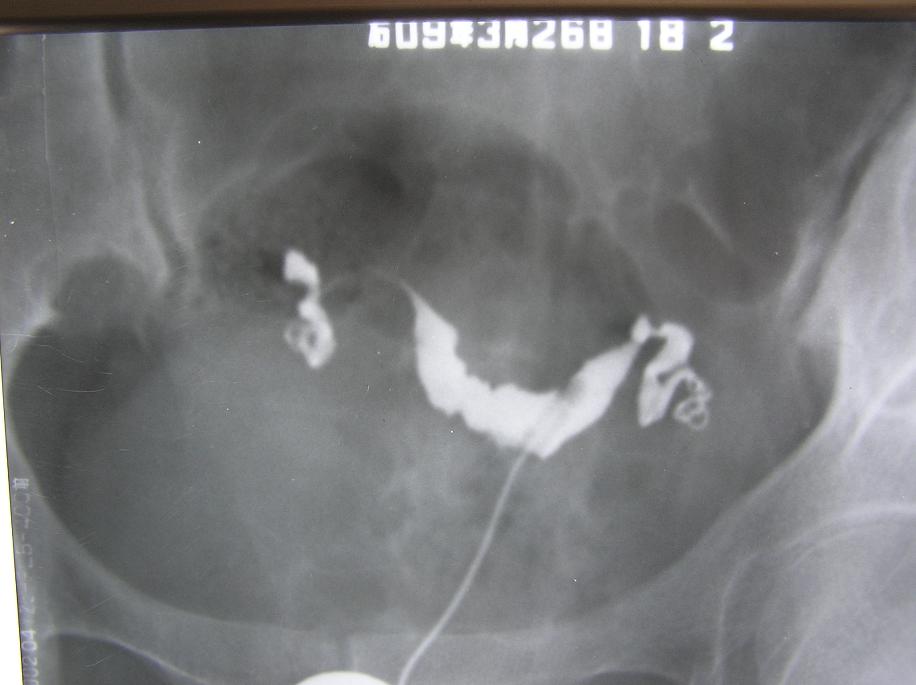

以下是引用杀毒软件在2009-3-27 18:22:00的发言:[br]比较严重的---宫腔粘连,整个宫腔看起来似---双角子宫,弥散像造影剂多在宫旁及输卵管旁,右侧输卵管僵直,壁上有小突起。[br][br]首选考虑----双侧慢性输卵管炎----〔宫腔粘连,输卵管周围粘连〕。 病人应该有很重盆腔炎。[br][br]因为单纯宫腔粘连,输卵管表现可保持正常,但此例子宫及输卵管都有明显改变的表现----不能排除---结核,建议---ppd。[br]

以下是引用随光逐影在2009-3-28 7:59:00的发言:[br]考虑为:1)鞍形子宫。2)宫腔炎。3)双侧慢性输卵管炎。